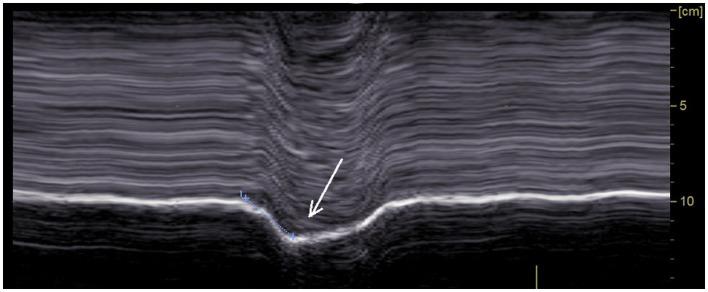

On paralyzed hemidiaphragm, thickening was less than 20% in all patients during deep inspiration. Thinning was recorded in 53% of cases. In some cases, the recording of the thickening could be difficult. The study of motion during voluntary sniffing reported a paradoxical excursion in all but one patient. During quiet breathing, an absence of movement or a paradoxical displacement was observed. During deep inspiration, a paradoxical motion at the beginning of inspiration followed by a reestablishment of movement in the cranio-caudal direction was seen in 82% of cases. In some patients, there was a lack of movement followed, after an average delay of 0.4 s, by a cranio-caudal excursion. Finally, in 4 patients no displacement was recorded. Evidence of hyperactivity (increased inspiratory thickening and excursion) of contralateral non-paralyzed hemidiaphragm was observed.